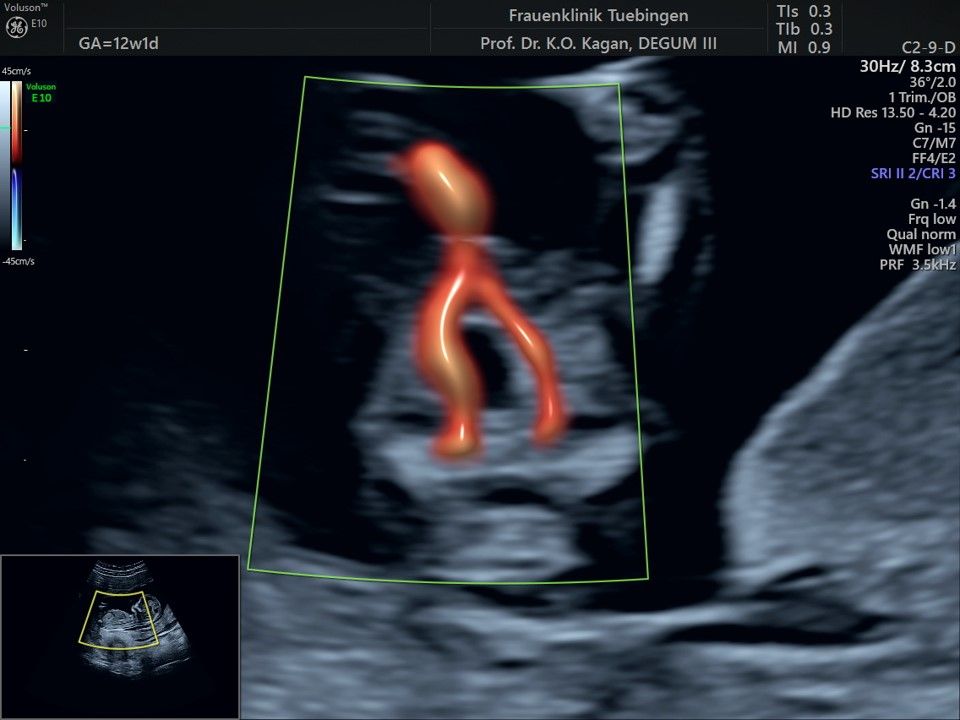

Mithilfe des Ersttrimester-Screenings kann das persönliche Risiko einer Präeklampsie bestimmt werden. Dazu wird die Vorgeschichte der Schwangeren, der aktuelle Blutdruck, das Ergebnis der Ultraschalluntersuchung (Widerstand in den Gebärmutter-nahen Gefäßen) und der Blutabnahme bei Ihnen (PAPP-A) kombiniert. Sollte das Risiko über 1:100 sein, empfehlen wir die tägliche Einnahme von Aspirin 150mg bis zu 35.SSW und eine gezielte Überwachung der weiteren Schwangerschaft.

Das Ergebnis der Ultraschalluntersuchung ist wegweisend. Dabei wird der Fet vermessen, die Organe werden untersucht und die sonographischen Marker zur Risikoberechnung für Chromosomenstörungen werden beurteilt. Das sind: die Nackentransparenzdicke, Nasenbein sowie der Blutfluss in der rechten Herzhälfte und im Ductus venosus, einem Gefäß in der Leber des Feten.